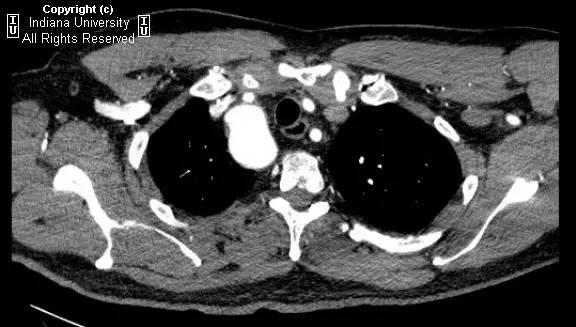

【影像学表现】胸部平片示右位主动脉弓,肺动脉突出,双肺清晰。CT示右位主动脉弓,并右位降主动脉,迷走左锁骨下动脉起自后方,从食管后走形形成血管环。迷走左锁骨下动脉与憩室相关(Kommerell)。食管因左锁骨下动脉及憩室而向前移位。

【诊断】右位主动脉弓并血管环形成、迷走左锁骨下动脉并Kommerell憩室

Right-sided aorticarch, with vascular ring and aberrant left subclavian with Kommerell\’sdiverticulum